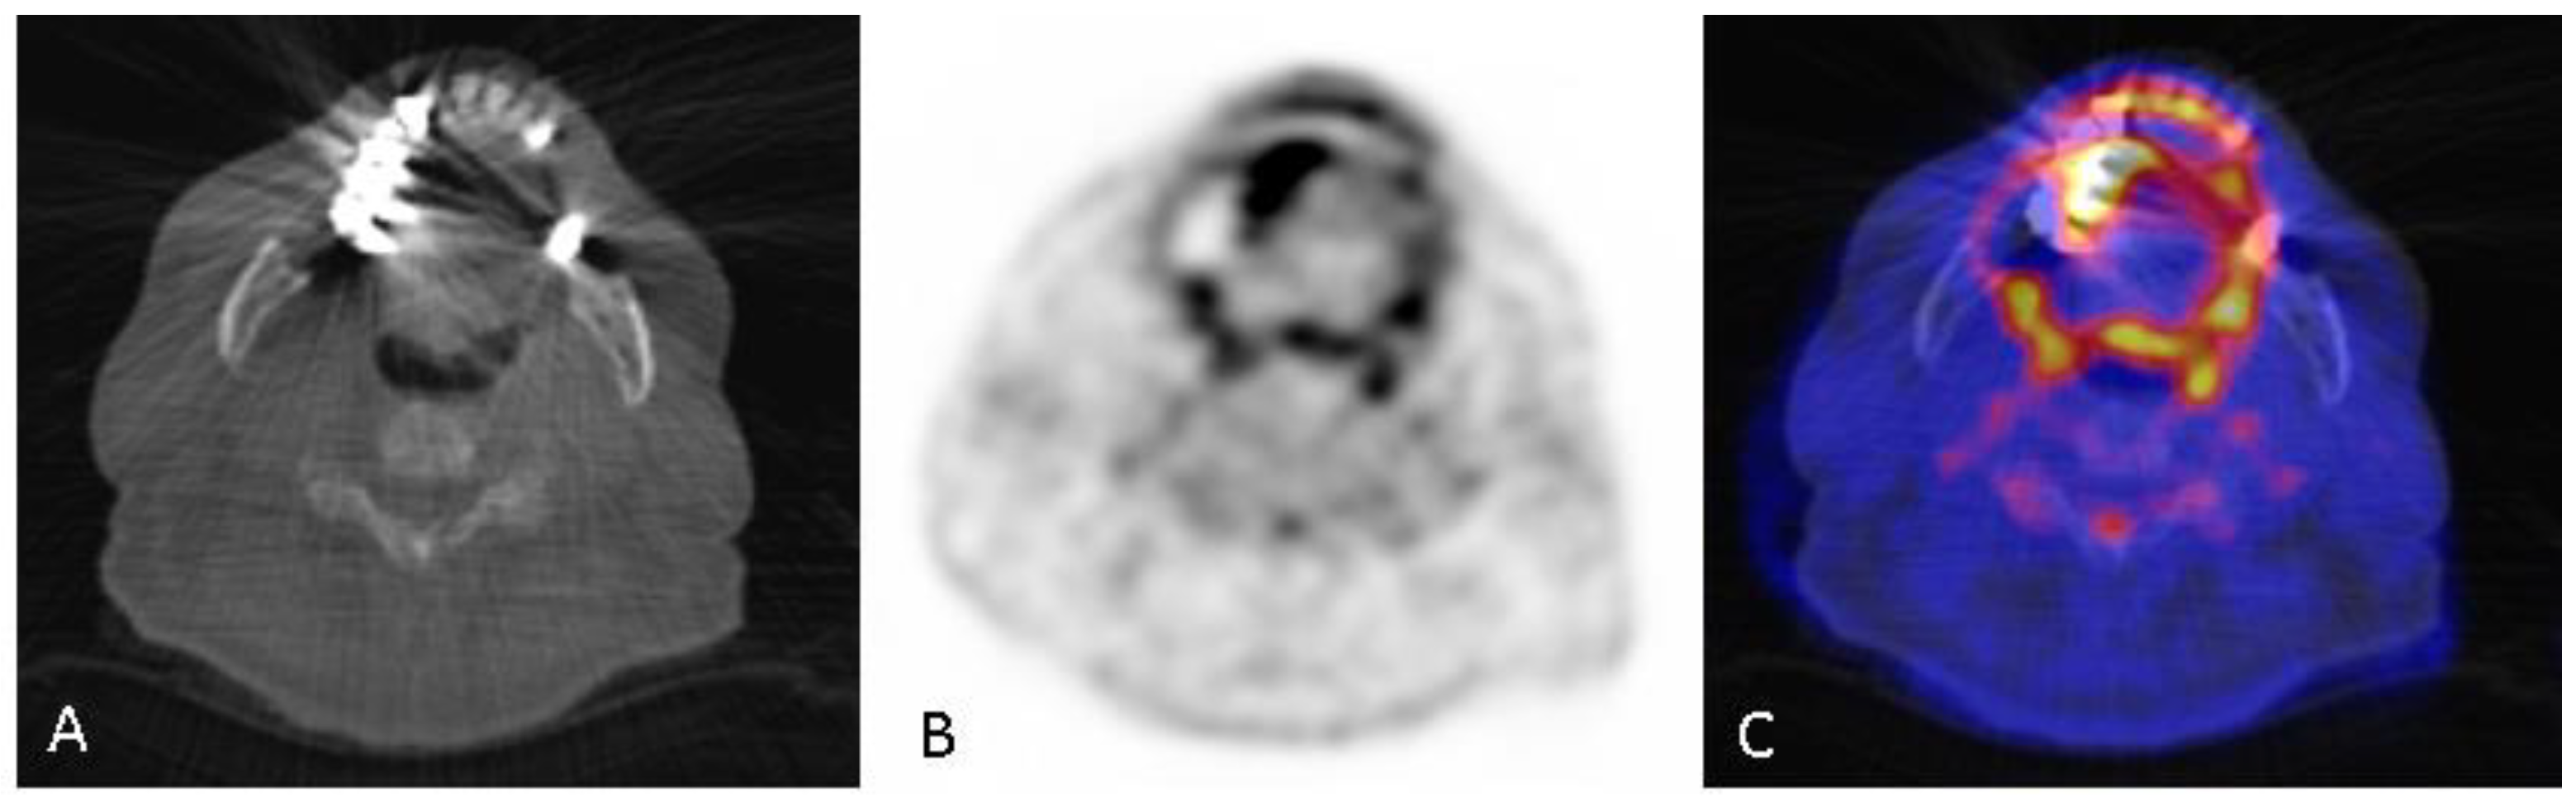

2.4. [18F]FDG PET/CT Scan Analyses of the Oral Cavity and Extra-Cardiac Areas